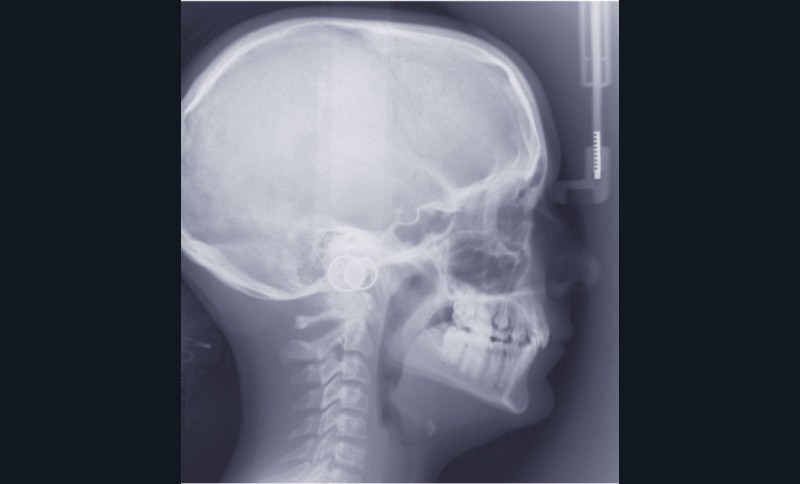

L’examen clinique exo-buccal révèle un visage équilibré en classe I squelettique tendance hypodivergente. De profil, le menton est marqué et le profil sous nasal très légèrement concave (fig. 1).